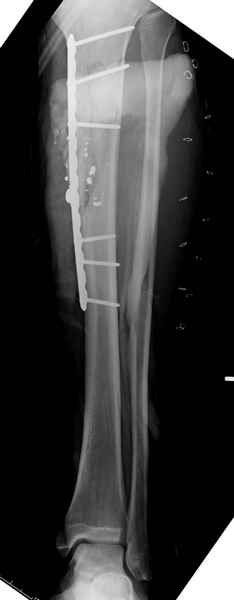

Из имеющегося под рукой - моё наблюдение из бурных 90-х.

Высокоэнергетическое ранение (калаш), обошелся вообще без ПХО. Полное восстановление оси, длины и функции. Правда, дольше обычного - больше полугода ходил в аппарате.

1 неполный перелом большеберцовой кости перкутанная пластина

2 перелом бедра